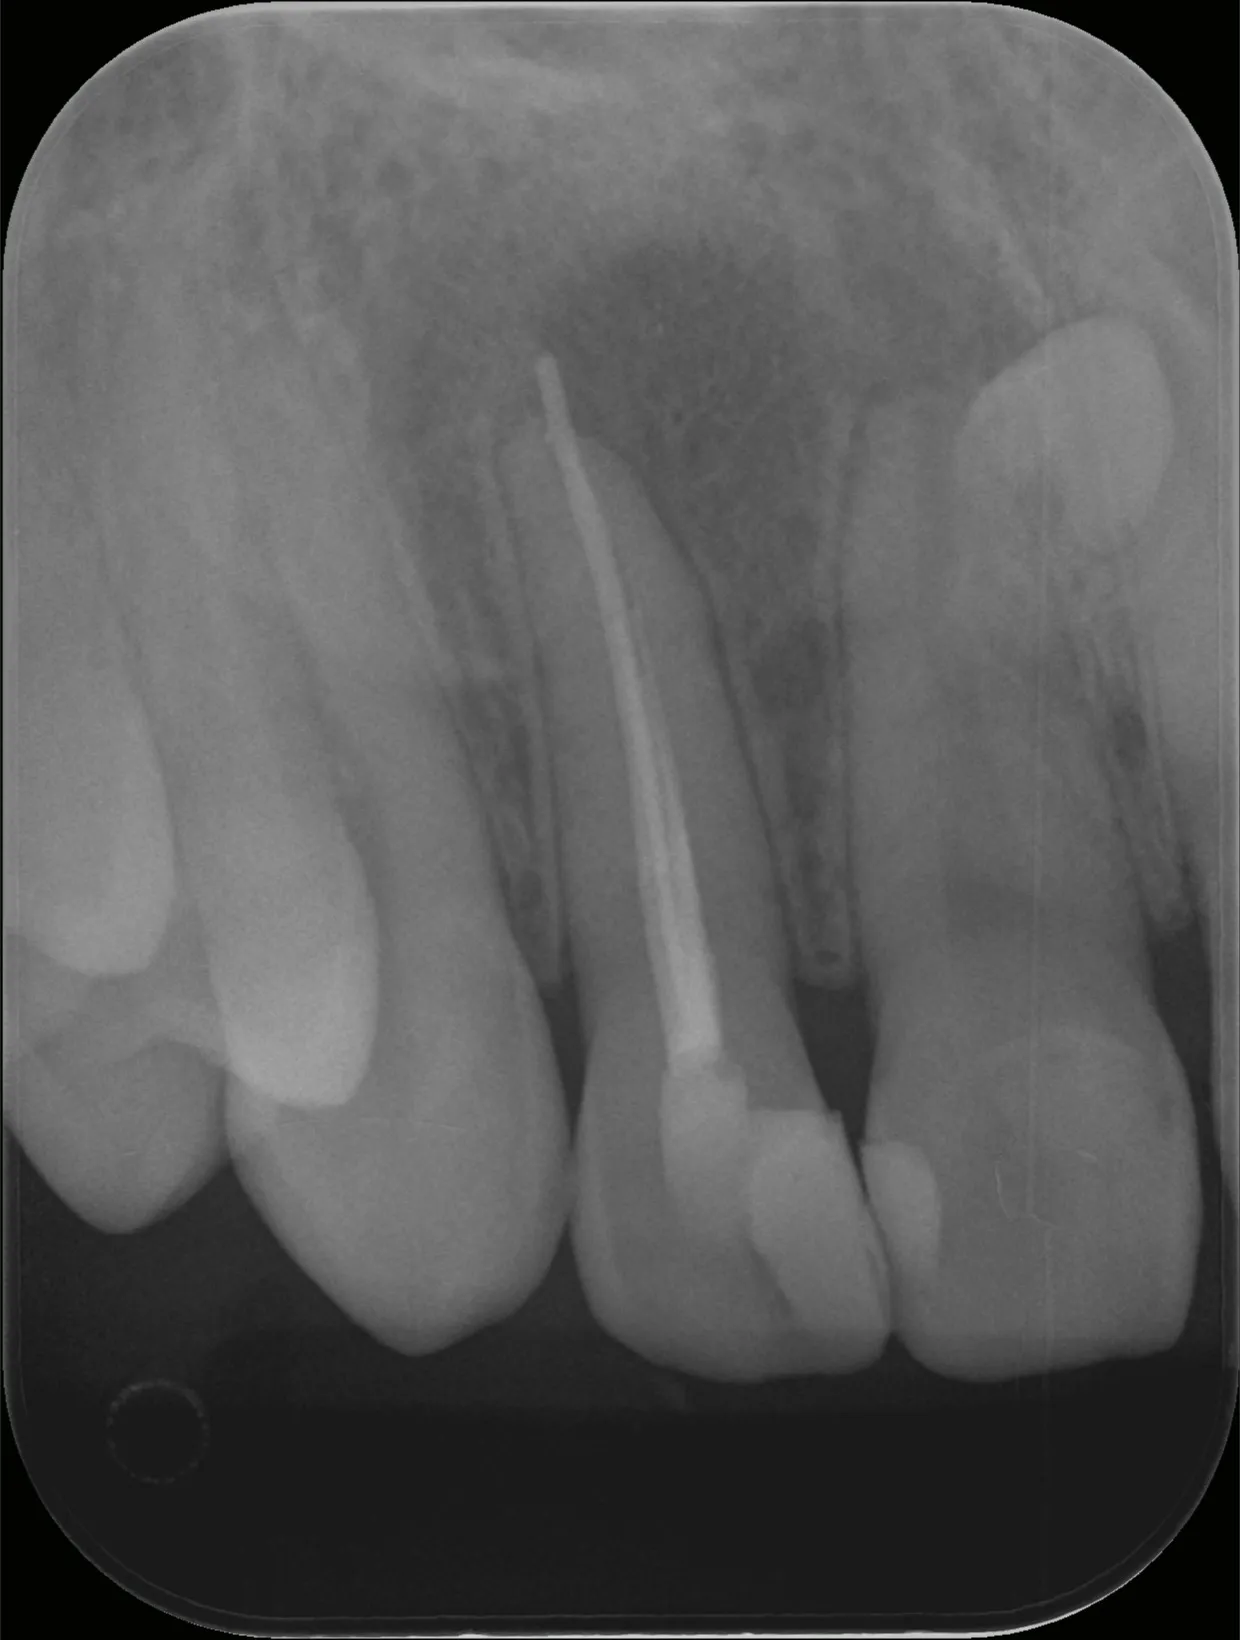

巨大な歯根膿瘍の根管治療1.5年経過症例

歯の根っこの先に膿ができる病気を歯根膿瘍、または袋状になった物を歯根嚢胞と言います。

今回は歯根膿瘍で上あごが大きく腫れてしまっていた状態の治療とその経過についてご紹介いたします。